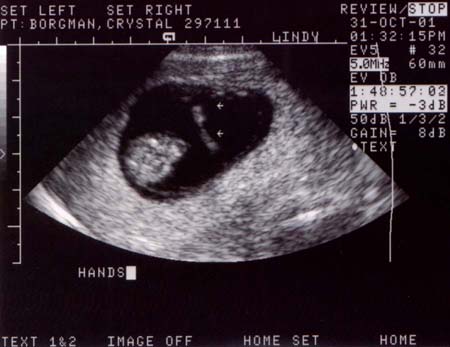

First ultrasound.

The baby looks great! It was moving around and having

a good old time. It measured at 10 weeks and 4 days,

or 37 millimeters (about 1 1/2 inches), which is just

about right. The heart rate was 188 bpm and very strong.

Looks like we've got a keeper.

Ultrasound Pictures:

Photo from top of

head looking down, baby's legs are crossed

Large

- 900x720 pixels / 66.1K

Small

- 450x360 pixels / 28.2K

head looking down, hands are together

- 900x700 pixels / 68K

- 450x350 pixels / 28.8K

Side profile, jaw

bones are prominent (the light areas)

- 900x720 pixels / 71.3K

- 450x360 pixels / 30.3K

Side profile, with

hand by face

- 900x600 pixels / 63.1K

- 450x300 pixels / 26.8K |